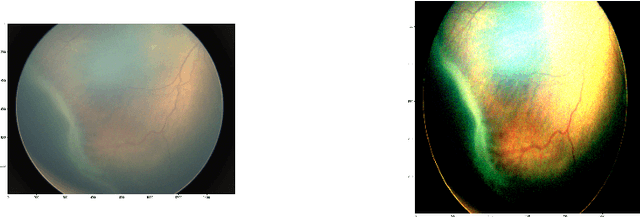

Abstract:Retinopathy of prematurity (ROP) is an abnormal blood vessel development in the retina of a prematurely-born infant or an infant with low birth weight. ROP is one of the leading causes for infant blindness globally. Early detection of ROP is critical to slow down and avert the progression to vision impairment caused by ROP. Yet there is limited awareness of ROP even among medical professionals. Consequently, dataset for ROP is limited if ever available, and is in general extremely imbalanced in terms of the ratio between negative images and positive ones. In this study, we formulate the problem of detecting ROP in retinal fundus images in an optimization framework, and apply state-of-art convolutional neural network techniques to solve this problem. Experimental results based on our models achieve 100 percent sensitivity, 96 percent specificity, 98 percent accuracy, and 96 percent precision. In addition, our study shows that as the network gets deeper, more significant features can be extracted for better understanding of ROP.